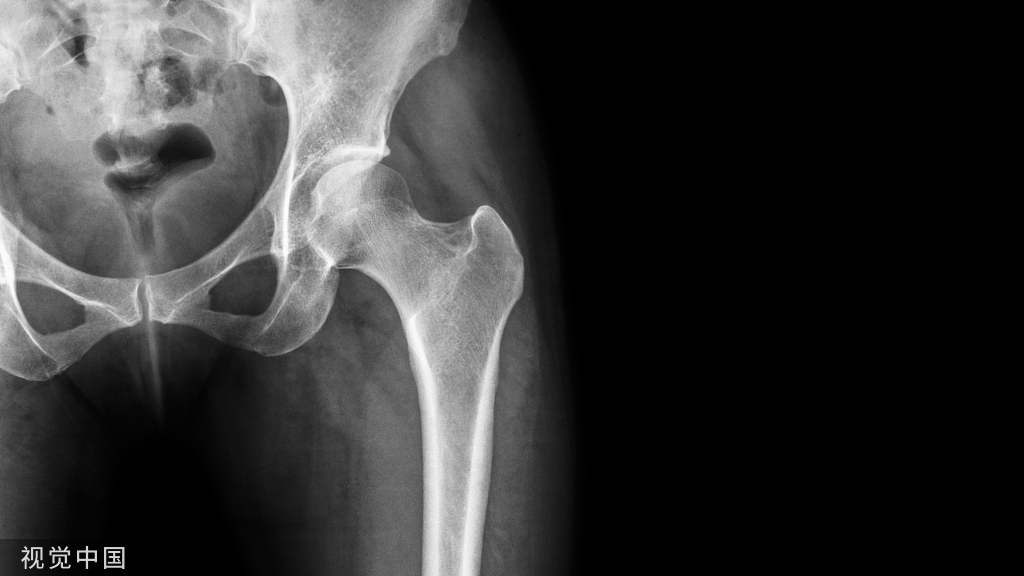

(一)解剖基础

下颌骨由下颌体及下颌升支两部分组成,似马蹄形;

下颌体分为内面、外面、牙槽突和下颌体下缘;

下颌升支由喙突、髁突、内、外面四部分组成;

下颌骨牙槽突的内侧骨板和外侧骨板都由骨密质构成,松质骨被内外侧骨板包绕其中。